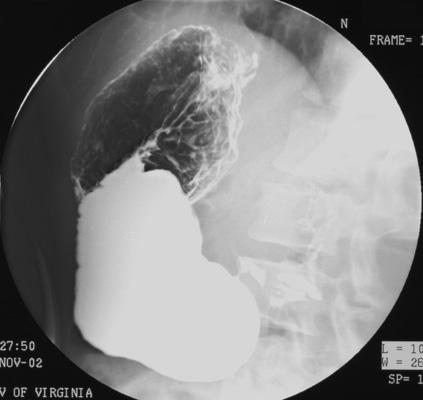

- Have patient make another counter-clockwise rotation

(as viewed from foot of table) to refresh the barium coating of the gastric

mucosa. Stop in the steep LPO position.

- Take four DC spot images

of the entire stomach using the largest FOV in the following sequence: